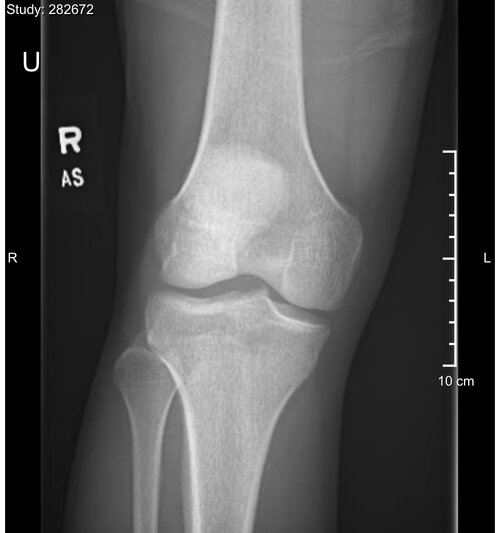

So I am a fucking disgusting manlet chud tho i have slayed a few mtbs. However, most of them have been my height and a couple shorter than me. Howver, I stg the ones my height always act like they run shit bc im a fucking manlet and ts pmo. I got my knees and wrists xrayed, they look fucking closed but currently am lying to myself and optimizing placebo or some fuckshit. they are attached below. I know it says 2010 for bday but like im a currycell whose parents fucked with my bday on immigration